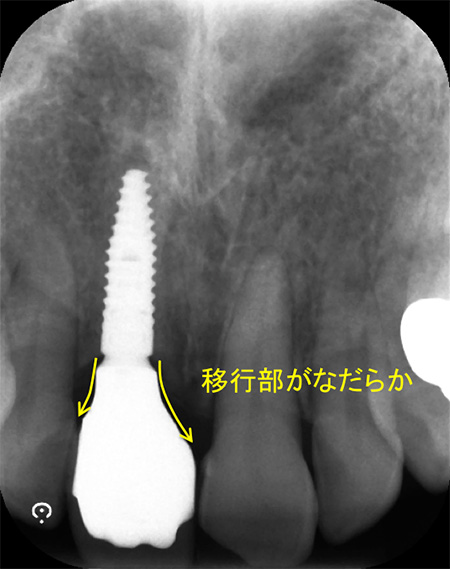

このX線写真のようにネジの位置が適切であれば、土台の移行部がなだらかで磨きやすい形と言えますが、このネジの位置が浅かったり、土台に急な角度がついてしまうとご自身でのブラッシングが困難になります。

(他院で治療されたインプラントです)

この急角度のくびれている部分までご自身でしっかり磨くのは、かなり困難と思われます。

このようにインプラントのポジションが1mmズレただけでも磨き易さは変わります。

当院ではインプラントのポジションを0.数mm単位で調整して手術を行います。